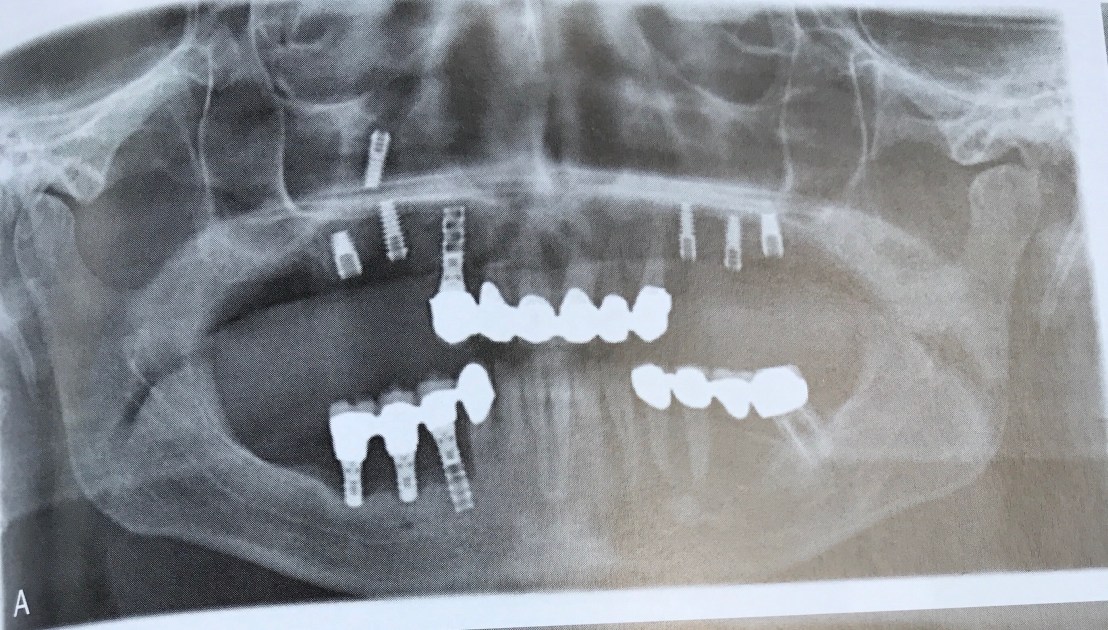

Implant 14 มีการเคลื่อนตัวเข้าไปอยู่ใน Max. sinus

เคสนี้ก็ขยับ แต่เคลื่อนสูงขึ้นไปอีก คือไปที่ Cranial base เลย

แสดงสาเหตุที่ทำให้เกิดการ Displace 4 ประการ คือ

A Bone density คุณภายแย่มาก

B ต้องทำ Bone graft ก่อน แต่ไม่ทำ

D จาก Peri-implantitis

E ไม่มี bone support

การแก้ไข กรณีเคลื่อนเข้า sinus ครับ ใช้วิธีส่องกล้อง FESS (Fucntional Endoscopic Sinus Surgery)